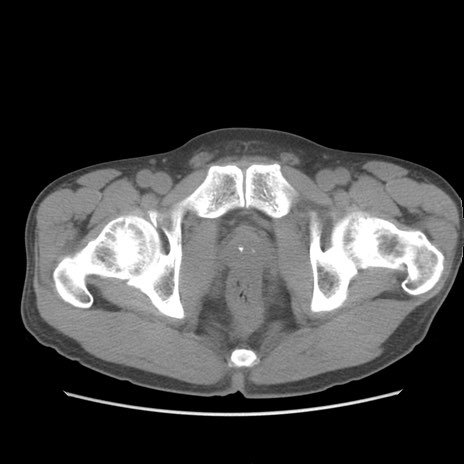

症例56 CT(横断像)

脂肪ウインドウ